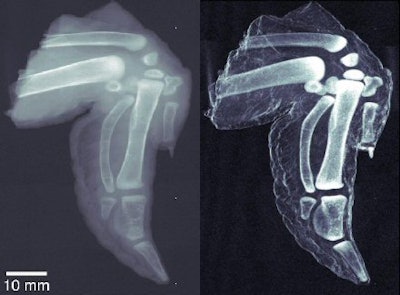

The images the group has produced so far indicate sharply higher image quality for dark-field x-rays when compared to images produced with conventional absorption-based techniques. Pfeiffer said the difference isn't so much higher spatial resolution for the dark-field technique; rather, certain types of structures -- such as very small cracks or abrupt edges -- produce scatter radiation that shows up well on dark-field images.

| At left, conventional radiography image of chicken wing. At right, dark-field x-ray image of same chicken wing. Images courtesy of Franz Pfeiffer, Ph.D. |